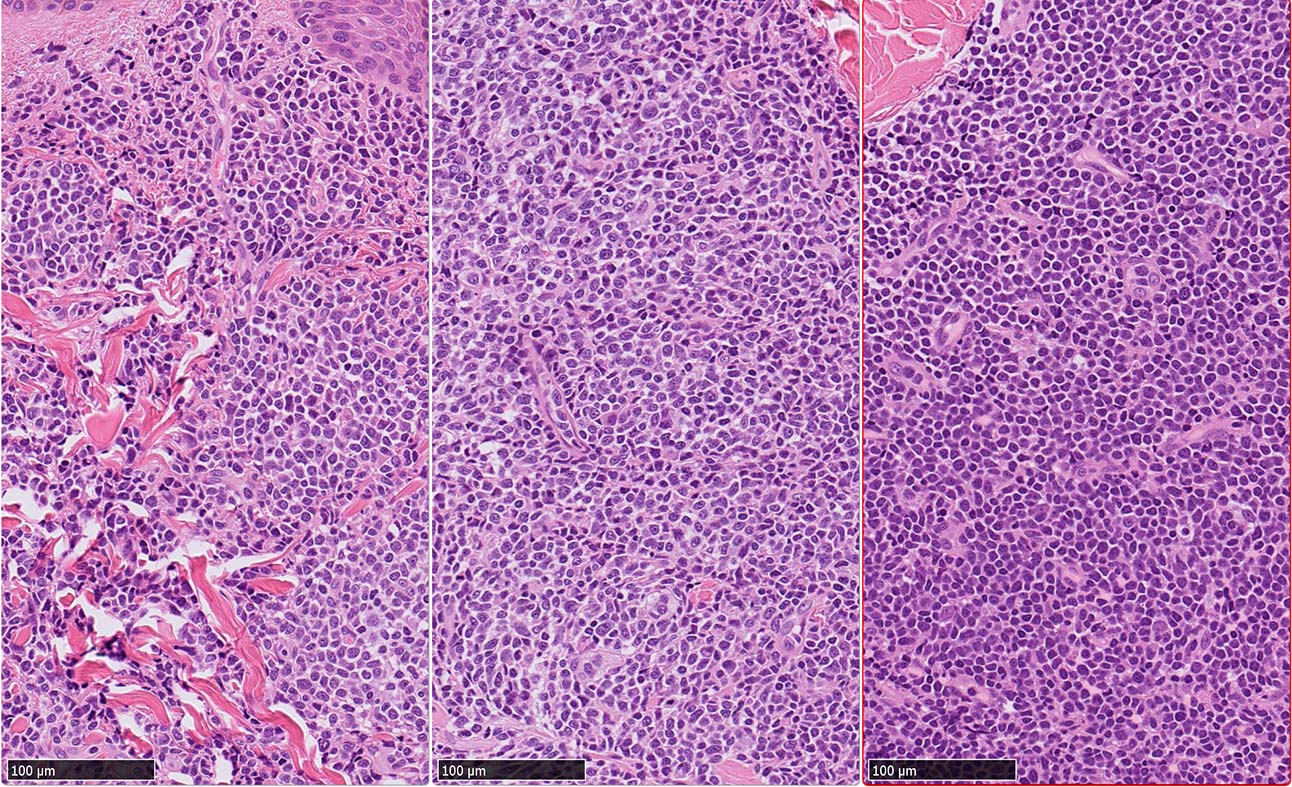

皮膚病変

blasticという名前から「大型細胞」を想起するが, この症例のようなclassical typeの細胞は思ったほど大きくはない. CD123陰性リンパ球とくらべてもあまり大きくないことがわかる.(散在する大型細胞はlysozyme+)

形態は均一で多型はめだたない.

BPDCNの増殖細胞形態

BPDCN 腫瘍は形態の異なる2種類の細胞の均一単調な増殖からなる.*4 本例はclassical BPDCNとなる

1. classical BPDCN

腫瘍細胞核は中等大, 不整形. クロマチンは繊細で, 核小体は不明瞭か, 1ないし数個. 細胞は狭小から中程度の量の細胞質をもつ.

2. immunoblastic BPCDN*2*3*4

類円形空胞状核, 好塩基性で中等量の細胞質,大きな光輝性の中心性核小体を1個もつ免疫芽球(immunoblast)に似た細胞の増殖が主体.